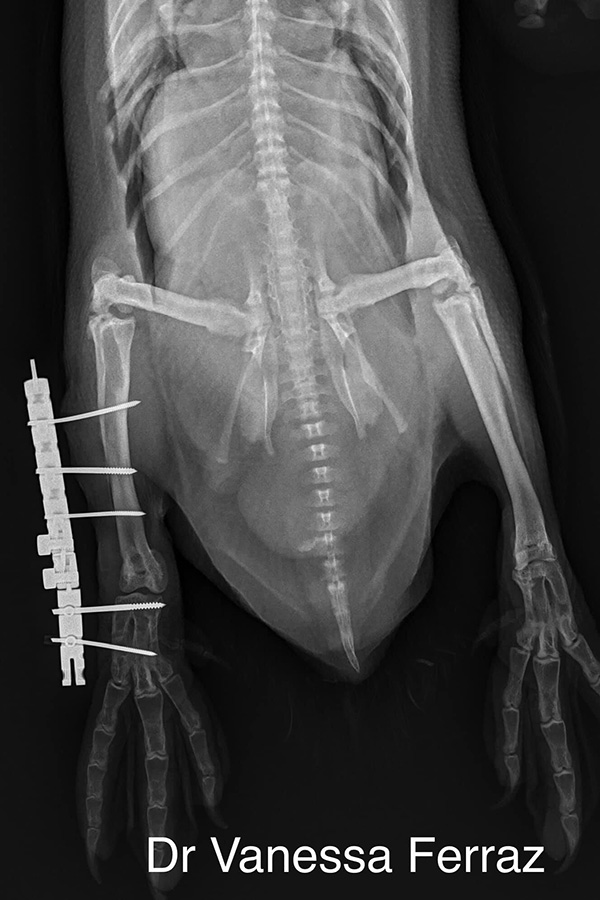

“We removed the fixator in less than 20 days and he was already walking a lot better. Once we removed the fixator, he was isolated for another week and then he was back with his penguin pod and doing very well,” she explains.

Ultimately, the successful outcome came down to a combination of Ferraz’s inventiveness and the AO principles related to anatomical positioning and preservation of the joint.